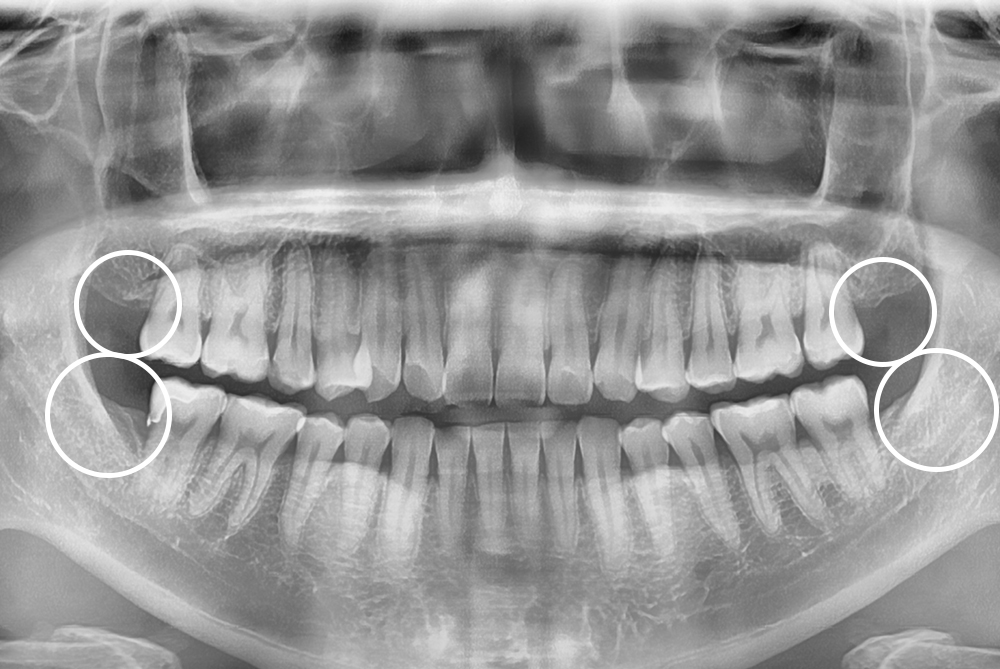

[사랑니] 매복 사랑니 발치

치료전 : 2019-12-14